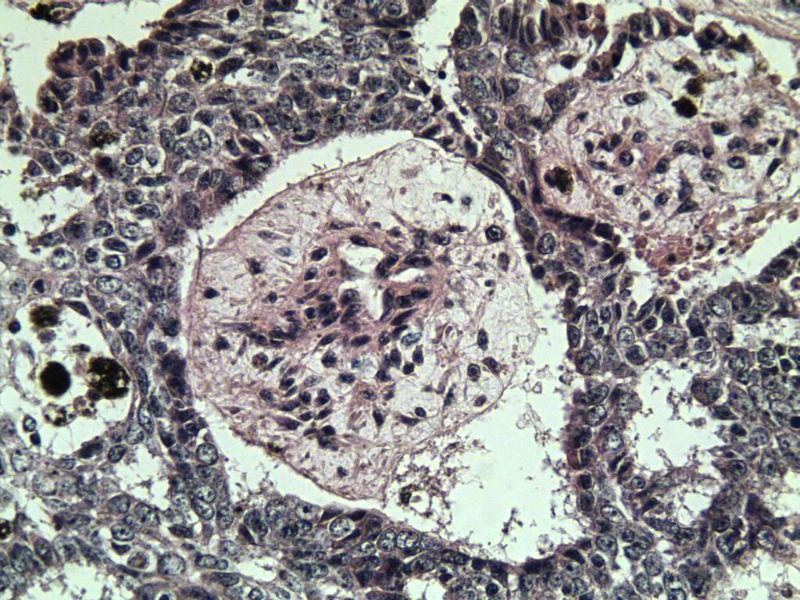

女 67岁 临床考虑面部色素痣 1*0.8 cm  请问各位老师 这是什么? 谢谢!面部包块图1

毛母/发细胞瘤鉴别基底细胞癌,可做CD10,CK7,CK20鉴别

考虑毛发上皮瘤,需除外基底细胞癌。

毛发上皮瘤,需与基底细胞癌鉴别

第一例:毛发上皮瘤

第一例:毛发上皮瘤,与基底细胞瘤区别明显。

第一例  毛发上皮瘤,和基底细胞癌鉴别一下

第一例考虑毛母细胞瘤,第二例考虑基底细胞癌。

毛母细胞瘤

第一例:毛母细胞瘤;第二例:基底细胞癌

第一例,毛发上皮瘤;第二例,基底细胞癌。

一毛发上皮瘤